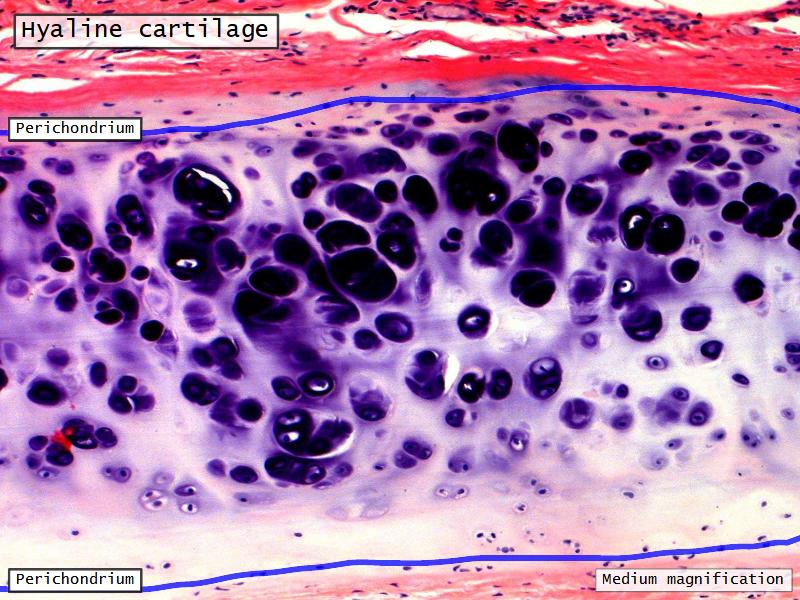

Epiglottis